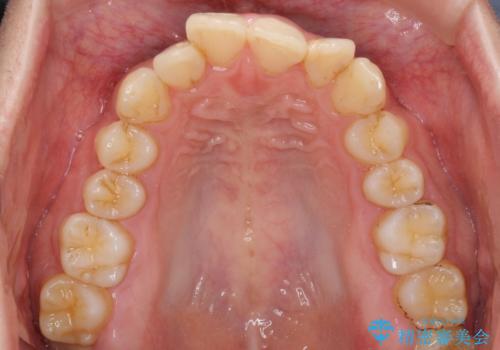

前歯のデコボコをスッキリ改善 インビザライン矯正

- 上下前歯のデコボコを気にして来院された患者様です。

全体的に叢生は軽度であったため、インビザラインにて矯正治療を行うこととしました。

デコボコの改善はもちろん、下顎前歯が隠れてしまうディープバイトも一緒に改善することができ、奥歯への負担を軽減することができました。